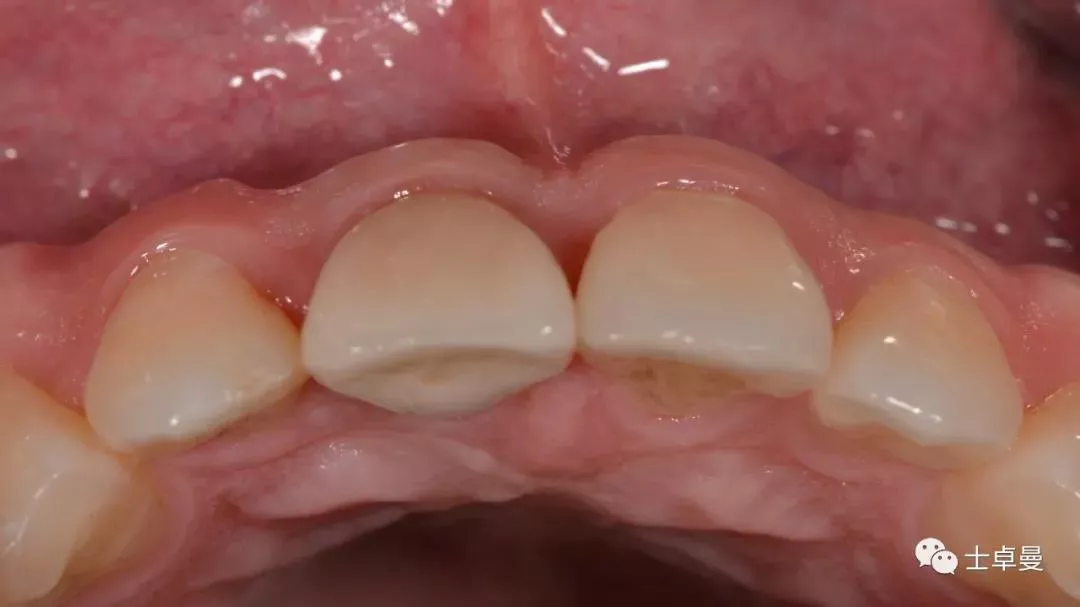

术后10天复查,软组织无炎症

术后1个月,取下马里兰桥,可见骨弓轮廓可,软组织无炎症